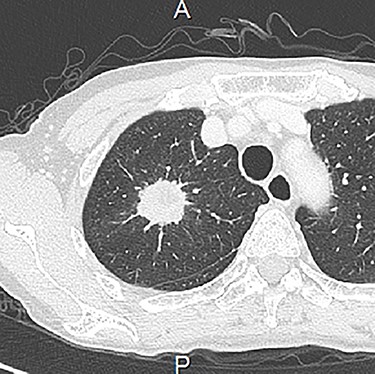

A 62-year-old woman was referred to our hospital due to suspected lung cancer. The chest CT revealed a 32-mm solid pulmonary nodule in the right upper lobe without lymph node enlargement (Fig. 1). The 3D-CT revealed that the right upper pulmonary vein (V1 + 2) ran posterior to the pulmonary artery and anterior to the bronchus intermedius (Fig. 2A and B). On the other hand, anterior segmental vein (V3) had venous return anterior to the top of hilum. Based on this information, we performed right upper lobectomy with systemic lymph node dissection under VATS. Intraoperative findings showed that the V1 + 2 drained to the left atrium between the main pulmonary artery and the bronchus intermedius (Fig. 3), which was clearly detected by the preoperative 3D-CT. We exposed the pulmonary vessels at the hilum and V3 was found superiorly on the most ventral side of the hilum, whereas we could not identify V1 + 2, which is usually located anterior to the hilum. After the V3 and the ascending pulmonary artery were ligated, we recognized the V1 + 2 at the dorsal side of the main pulmonary artery. The anomalous V1 + 2 were isolated and ligated with a vascular stapler. Therefore, it was possible to complete VATS lobectomy without any complications. Pathological examination showed adenocarcinoma with no lymph node metastasis. The postoperative course was uneventful, and the patient was discharged on postoperative day 7.

Chest CT showed a 32-mm diameter solid mass in the right upper lobe.